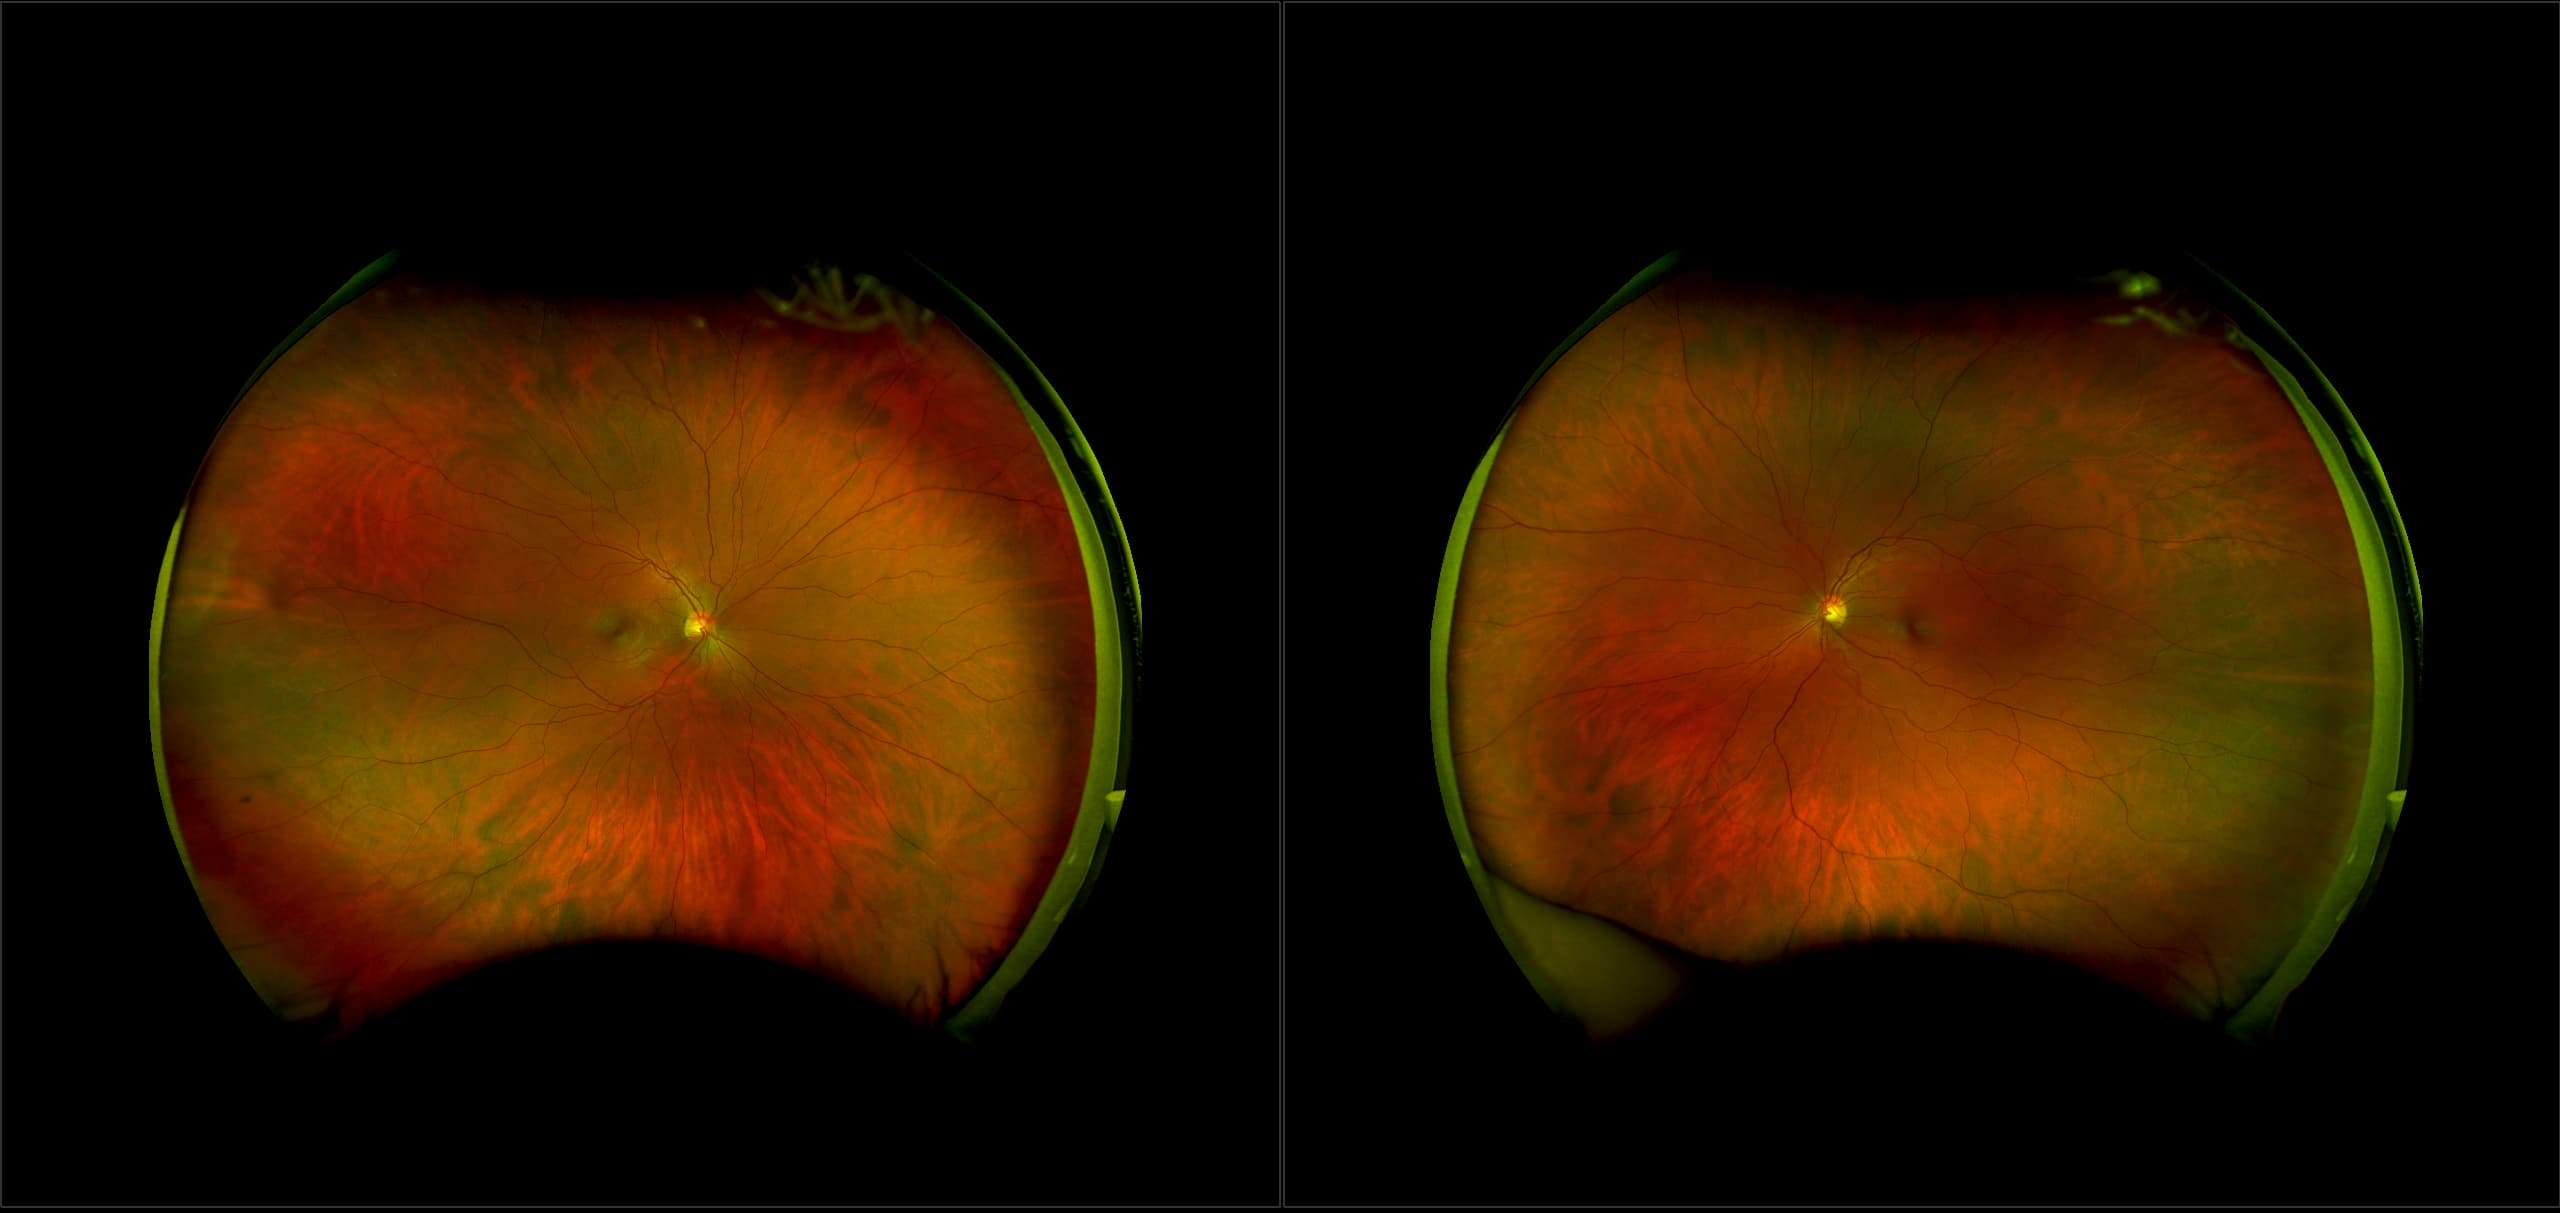

California - Large Pars Plana Cysts - Steered, RG

Pars plana cysts are a common peripheral retinal pathology that do not raise much clinical concern. They do not affect the central vision and observation alone is typically recommended. Pars plana cysts are something to be considered when peripheral retinal elevation is noted on routine exam.